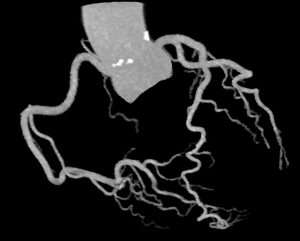

冠動脈CT

造影剤を用いて撮影することにより、心臓を栄養している動脈(冠動脈)の狭窄や閉塞によって起こる、狭心症の評価や予防に有用です。

VR表示

MIP表示